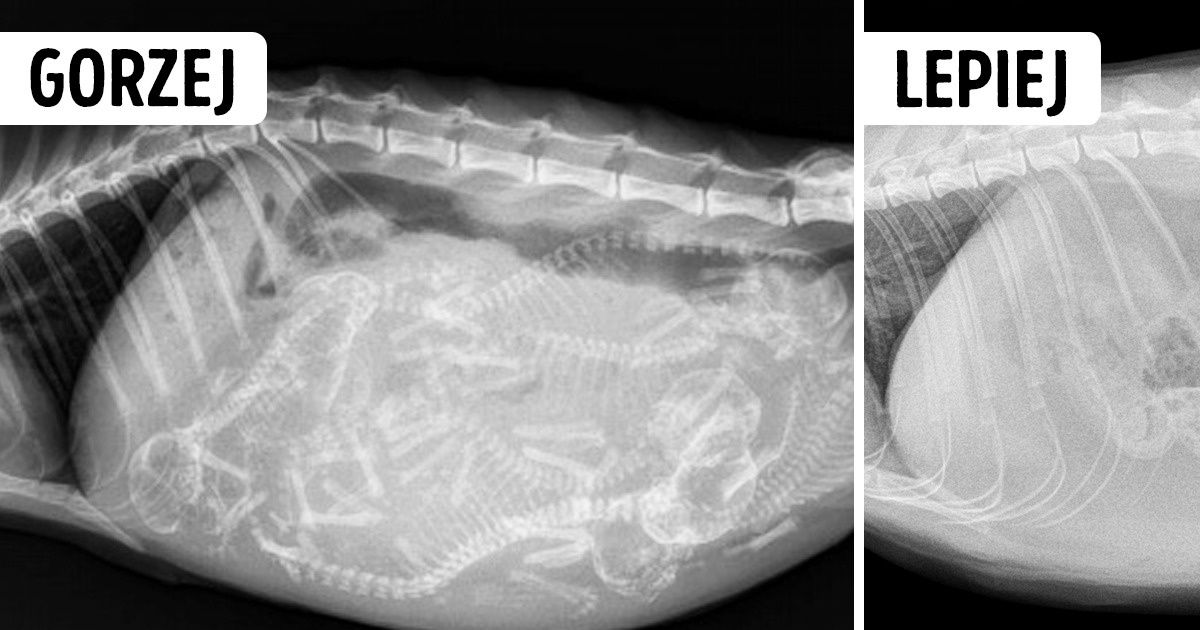

Zdjęcie na górze: zdjęcie rentgenowskie ciężarnej kotki.

Zdjęcie na dole: zdjęcie rentgenowskie wysterylizowanej kotki.

W większości przypadków zabiegi te mają pozytywny wpływ na zdrowie kota. Zmniejszają ryzyko guzów sutka u kotek i guzów jąder u kotów. Co więcej, koty wykastrowane nie mają skłonności do agresji ani uciekania z domu.